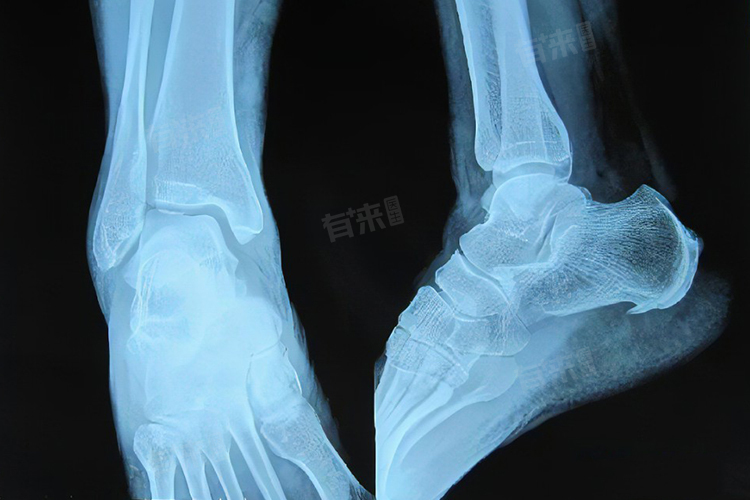

- 年龄增长:随着年龄的增加,人体的骨骼会发生退变,足跟部位的软骨、骨质等结构也逐渐老化。关节软骨磨损后,机体为维持关节的稳定性,会在足跟骨的边缘形成骨刺,这是自我修复的表现,但可能会引发疼痛等症状。

- 足部结构异常:如扁平足、高弓足等足部畸形,会改变足部的力学分布,正常的足弓可以缓冲行走时的冲击力,而足部结构异常时,足跟部位受力不均,局部压力集中,容易引发骨质增生形成骨刺,也可能伴随足底筋膜炎等其他足部疾病。